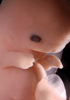

Carnegie Stage 19 (47 post-ovulatory days)

Most embryos at stage 19 are approximately 47-48 post-ovulatory days old and measure 17-20 mm in length. Distinguishing criteria for this stage include straightening of the trunk, the limbs extend nearly directly forward, toe rays are prominent, but interdigital notches have not yet appeared in the foot.

Although some of the photographs below show abnormal embryos, the animations and MRI slice images all depict normal embryos. Abnormal embryos are noted in the titles of the large photos when they are opened.